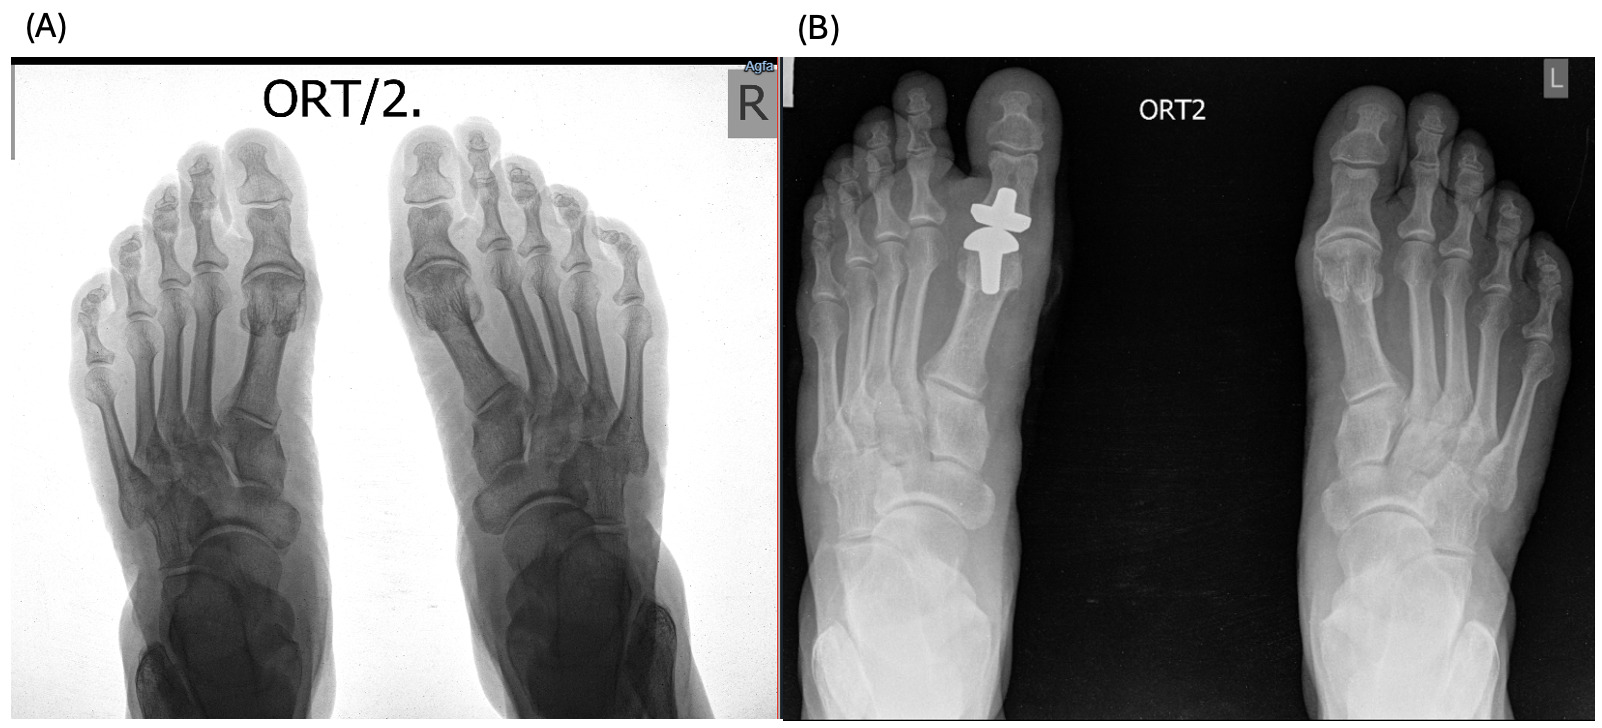

A 61-year-old female patient with a history of trauma on the left first MTP presented to the clinic with complaints of pain and limited range of motion of the right foot first MTP for the last several years. The patient was receiving conservative treatment within the last year with temporary relief; therefore, the surgical intervention was recommended and the patient was referred to our clinic. Physical examination revealed almost no movement and pain on palpation, as it can be seen on Figure 1 (A).

After the total first MTP replacement using ceramic implant, 2 and 6 months later, there is preserved improvement in the joint mobility, absence of pain and discomfort during movement (Figure 1 (B, C)). The patient reports satisfaction with the use of joints.

A 63-year-old female patient with a limited range of movement in her right leg, pain during walking or using stairs for the last 1 year, reports significant worsening of the pain after stepping incorrectly 2 weeks ago, with a temporary effect of NSAIDs. Physical movement revealed the movement for 10-15 degrees in the 1st MTP joint, accompanied by pain (Figure 2, A).

2 and 6 months after surgery, the patient reports mostly preserved mobility of the joint, absence of pain (Figure 2 B, C). In addition, the patient reports improvement of edema and a decrease in weight.

The patients had undergone radiographic evaluation of the MTP joint before the surgery, right after surgery, and 2 and 6 months after surgery (Figures 4-9). The radiographic imaging after the surgery confirmed the correct positioning and alignment. At the follow-up, the radiographic images were done to analyze the early healing process, to observe if there were any signs of implant loosening. 2 months after the surgery, no patient had periprosthetic radiolucencies, no stress-related changes. 6 months after surgery, no osteolysis, no migration of the implant.

This case series demonstrates successful short-term results following total first metatarsophalangeal (MTP) joint replacement using ceramic implants in patients with hallux rigidus. All three patients presented significant improvement in AOFAS scores within 2 months postoperatively, with preserved improvement at 6 months. Notably, Patient C, who had the lowest preoperative score (27/100), achieved the greatest relative improvement, reaching 92/100 at 2 months and 89/100 at 6 months. These functional outcomes were confirmed by physical examination findings, with clear improvements in joint alignment and reduction in deformity (Figure 1-3, (B, C)). Moreover, radiographic imaging revealed no signs of complications such as implant loosening, migration or stress-related changes.